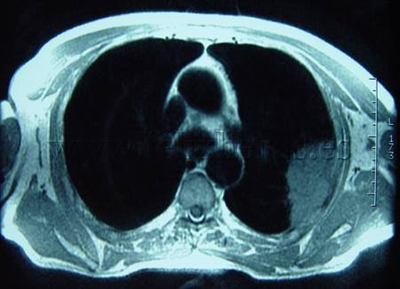

Cáncer de pulmón